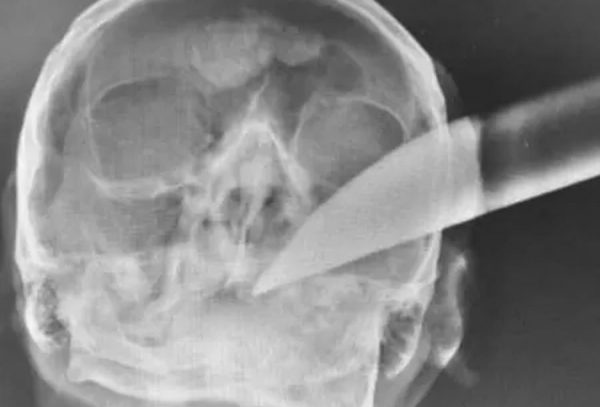

Raio-x mostra faca cravada na cabeça de homem e ele sobrevive

Um homem de 59 anos sobreviveu depois de ficar com uma faca cravada no lado esquerdo da cabeça.

Esse acontecimento inusitado ocorreu depois de uma briga na noite de quarta (16) em Mafra, cidade no norte de Santa Catarina. Uma imagem divulgada pela Polícia Militar mostra o raio-x da arma branca presa no crânio da vítima. O caso foi registrado na manhã de ontem e o principal suspeito foi identificado. De acordo com relato da Polícia Militar, apesar de a agressão ter acontecido na noite de quarta, a vítima só foi pedir ajuda para a vizinha, sobrinha dele, na manhã de ontem. O tio não soube dizer se havia passado a madrugada desmaiado.

A mulher acionou os bombeiros, que conduziram a vítima ao Hospital São Vicente de Paulo, consciente e orientado, ainda com a faca na cabeça. A PM também foi acionada. Na mesma noite de quarta-feira (16), a polícia catarinense atendeu a uma ocorrência de lesão corporal em outro bairro da cidade, onde um homem teria pedido ajuda em uma residência, com ferimentos no braço. Ele posteriormente foi identificado como o suspeito de ser o autor da facada, em posse da bicicleta da vítima internada.